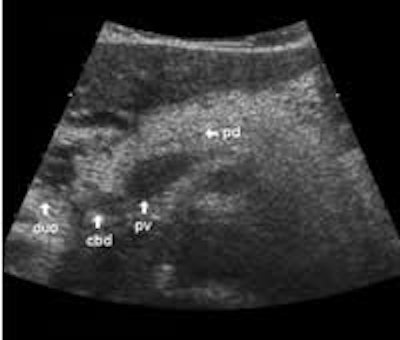

The following study describes anatomical landmarks in the ordinary pancreas of a thin patient:

Transverse planes in caudal direction:

The dorsal aspect of the head takes the shape of a hook surrounding the right side of the superior mesenteric vein; the sharp left-pointing tip of the hook behind the vein constitutes the uncinate process. The splenic vein runs from the left along the dorsal border of the tail and body to the superior mesenteric vein, where these veins join to form the portal vein behind the "neck" of the pancreas. The portal vein then leaves the pancreas to the right and slightly upwards and runs into the liver hilum.

The main bile duct runs from the liver hilum to the right of and above the portal vein into the right dorsal part of the pancreatic head, where it runs vertically into the duodenum. The pancreatic duct typically runs along the body and tail to join the common bile duct near the duodenum. The gastroduodenal artery is sometimes seen in its position along the front margin of the pancreatic head, where it runs in a nearly parallel direction to the common bile duct. Like the common bile duct and pancreatic duct, however, the gastroduodenal artery is not always clearly seen due to its small diameter. The duodenum covers the right and bottom margins of the pancreatic head.